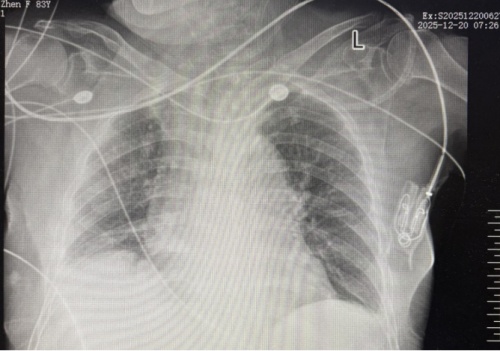

2025-12-20胸部 X线:支气管炎,主动脉硬化右膈面升高、右膈肌黏连。

结合患者症状、体征及辅助检查,高度怀疑肠坏死,建议行开腹探查术。家属签字同意后积极完善术前准备,予2025年12月20日11:50入手术室行“回肠切除术,腹腔脓肿切开引流术,小肠扭转复位木”。术后 14:30 返回ICU继续治疗,腹部敷料包扎完好,留置腹部左侧1根腹腔引流管及腹部左侧1根吻合口周引流管通畅。